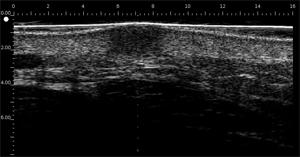

DERMCUP permite la adquisición no invasiva de secciones verticales de la piel in vivo

25 MHz: 16 mm x 12 mm